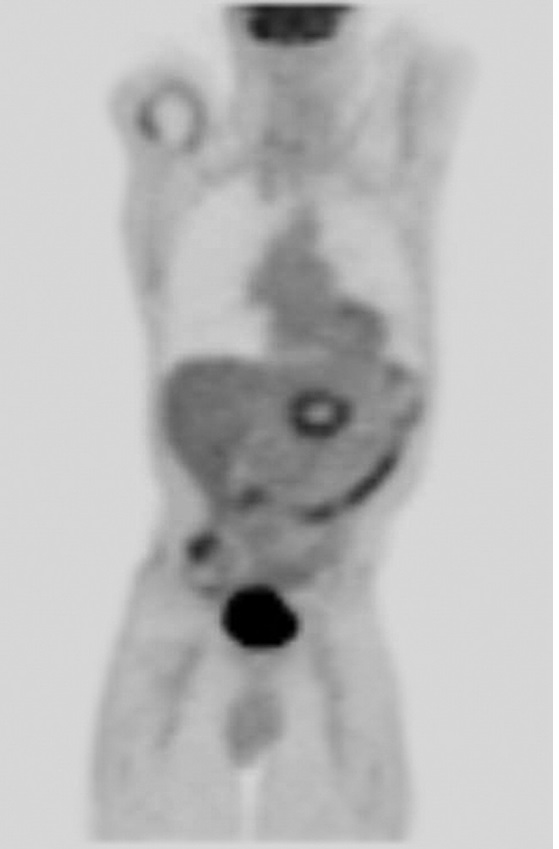

在隨后兩周的隨訪中,病人出現(xiàn)輕微間歇性疼痛,沒有出現(xiàn)疲勞,發(fā)燒或其他癥狀。每次消融后24小時(shí)之內(nèi)都使用對(duì)比增強(qiáng)磁共振成像(圖3),第二次消融后的30天預(yù)期消融區(qū)沒有出現(xiàn)增強(qiáng)。消融區(qū)的脈管系統(tǒng)尤其是脾動(dòng)脈和腸系統(tǒng)上動(dòng)脈保持明顯不變的術(shù)前外表。血清腫瘤抗原在消融手術(shù)后30天從1500U/mL減少到404U/mL90天達(dá)到407U/mL。診斷后使用PET/CT成像(圖4)如圖所示出現(xiàn)了一個(gè)輕微的氟脫氧葡萄糖周邊圈。雖然沒有觀測(cè)到參與腫瘤或節(jié)似疾病,但是在治療后的三個(gè)月PET/CT掃描出了1.5cm的肝轉(zhuǎn)移。因病變遠(yuǎn)離大血管在經(jīng)皮RF消融后肝轉(zhuǎn)移被成功治愈,然后開始吉西他濱化療。RF消融兩個(gè)月,診斷后六個(gè)月,磁共振成像顯示腹部沒有疾病惡化或復(fù)發(fā)。癌癥病源19-9水平六個(gè)月減少到236U/mL。

PET/CT image at 3 months. Smooth marginal uptake is seen, which is an expected finding after ablation. There is no focal residual disease in the pancreatic bed. Focal left hepatic

uptake is not well seen on coronal projection.